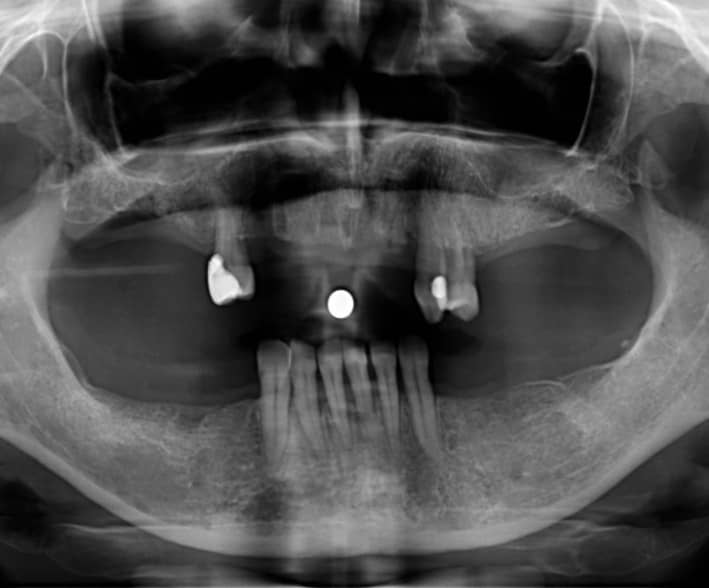

A vizsgálatok és röntgenfelvételek birtokában megbeszéltük, milyen lehetőségek jöhetnek szóba. A páciens az implantációt anyagilag nem tudta vállalni, illetve a megmaradt természetes fogait nem szerette volna bármilyen egyéb pótláshoz lecsiszoltatni, így végül az öntött kapcsos, kivehető pótlás mellett döntöttünk.

kapcsos részleges lemezes fogpótlás röntgenfelvétel